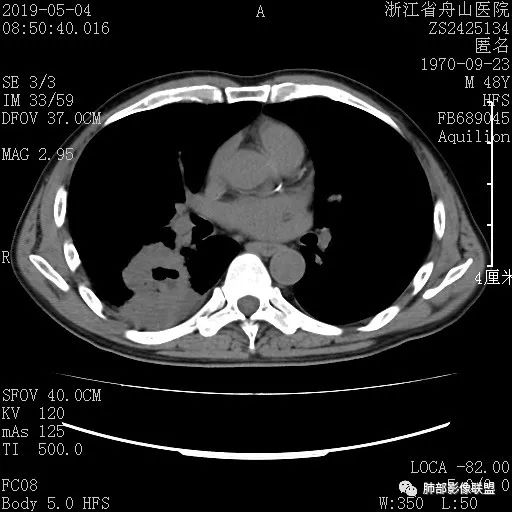

CASE 4 医学百科网 | YxBaike.Com

男 78 医学百科网 | YxBaike.Com

讨论

Clover: 医学百科网 | YxBaike.Com

错构瘤 医学百科网 | YxBaike.Com

光明: 医学百科网 | YxBaike.Com

实性结节,浅分叶,边缘光滑,挂果,考虑错构瘤 医学百科网 | YxBaike.Com

王秀仙:

右肺上叶后段实性结节,边缘光滑清晰,密度离散度大,考虑错构瘤

月影无踪:

边缘清,实性,浅分叶,血管贴边,良性结节,错构大过psp

以上二者如何鉴别呢?PSP与错构瘤

PSP 血管贴边,强化明显,晕,错构瘤没有

Clover:

有分叶支持错构瘤 医学百科网 | YxBaike.Com

血管贴边与挂枝头有所区别,血管贴边常常贴一会再走,挂枝头是贴一点点直接走了 医学百科网 | YxBaike.Com

离散度大

分叶,离散度大,错构瘤

边缘平直为主,彭隆感觉比较均匀,血管自然,支气管情况不明,倾向于良性。轻度凹陷,软骨型错构瘤第一位,炎性肉芽肿第二位。淋巴结未见,神经内分泌最后。

有黑晕,错构瘤

挂果征

SFT密度均匀,没钙化,没脂肪,应该离散度非常小 医学百科网 | YxBaike.Com

PSP也可以钙化,离散度有时也可以大 医学百科网 | YxBaike.Com

王兆宇: 医学百科网 | YxBaike.Com

病理诊断 医学百科网 | YxBaike.Com

血管贴边与挂果,分叶与光滑,可以作为鉴别吧

从我们二十几例PSP来看,PSP没有明确的分叶 错构瘤浅分叶常见,一般是软骨型错构瘤,因软骨团形成可以好几团或好几个软骨中心,所以有分叶

黑晕应该错构和psp都可以出现吧,应该不会作为鉴别点

@管洪林 对的,黑晕二者都可以有,以错构瘤多见,达70-80% 医学百科网 | YxBaike.Com

一句话小结: 医学百科网 | YxBaike.Com

肺部边缘光整结节影,孤立,有一定规模(大于1公分)且不在胸膜下,未见肺门纵隔淋巴结增大且没有原发肿瘤病史的,首先想到良性病灶。

病灶密度不均,或者说密度反差太大,即便未见典型的脂肪密度影或钙化亦应当首先先到错构瘤。 医学百科网 | YxBaike.Com

增强扫描有助于鉴别硬化性肺细胞瘤。 医学百科网 | YxBaike.Com